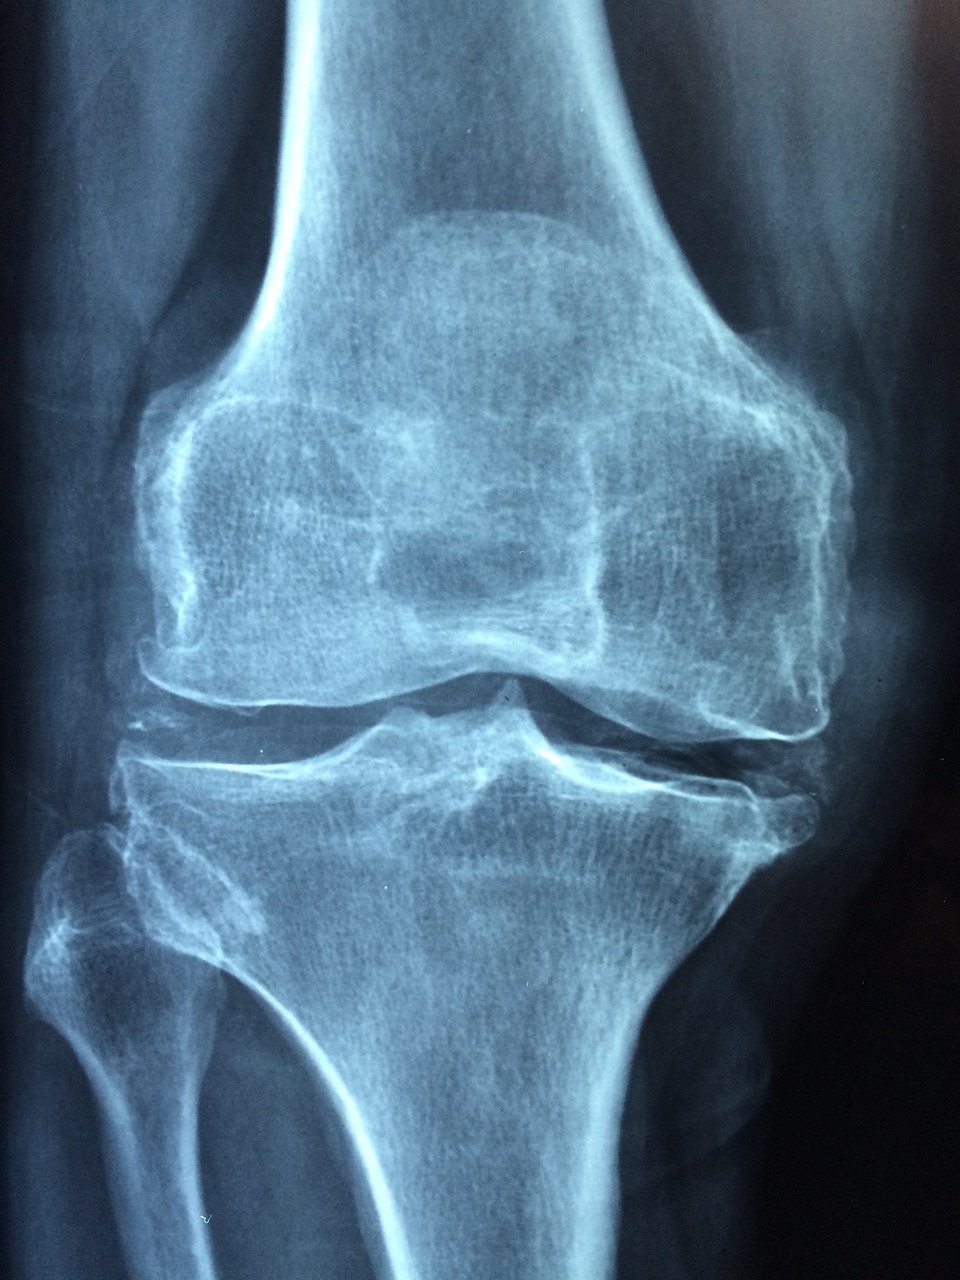

골다공증은 뼈의 밀도가 감소하여 뼈가 약해지고 쉽게 부러지는 질병으로, 주로 고령자에게서 발생하는 경우가 많습니다. 이 질병은 미리 예방하고 적절한 치료를 통해 관리해야 합니다. 이 글에서는 골다공증의 증상과 수치, 골다공증에 좋은 음식, 주사와 약물 치료의 부작용에 대해 알아보겠습니다.

골다공증은 초기에는 증상이 없거나 미미한 통증으로 나타날 수 있습니다. 하지만 진행되면서 뼈의 밀도가 떨어지고 뼈 조직이 약해지므로 다음과 같은 증상이 나타날 수 있습니다. 예방을 위해서는 평소에 건강한 식단과 적절한 운동을 유지하는 것이 중요합니다.

- 뼈의 부러짐: 골다공증으로 인해 뼈가 약해져서 간단한 충격이나 낙하로도 뼈가 부러질 수 있습니다.

- 뼈가 쉽게 부러지는 부위: 골다공증은 주로 골밀도가 높은 대퇴골, 팔뚝뼈, 골반 등에서 뼈가 쉽게 부러질 수 있습니다.

골다공증 수치는 골밀도 검사를 통해 측정할 수 있으며, 일반적으로 T-스코어로 표시됩니다. T-스코어는 표준편차로 나타내며, -1 이하이면 골다공증 가능성이 높다고 판단됩니다. 각 수준에 따른 관리 방안이 달라지므로 정기적인 검진이 필요합니다.